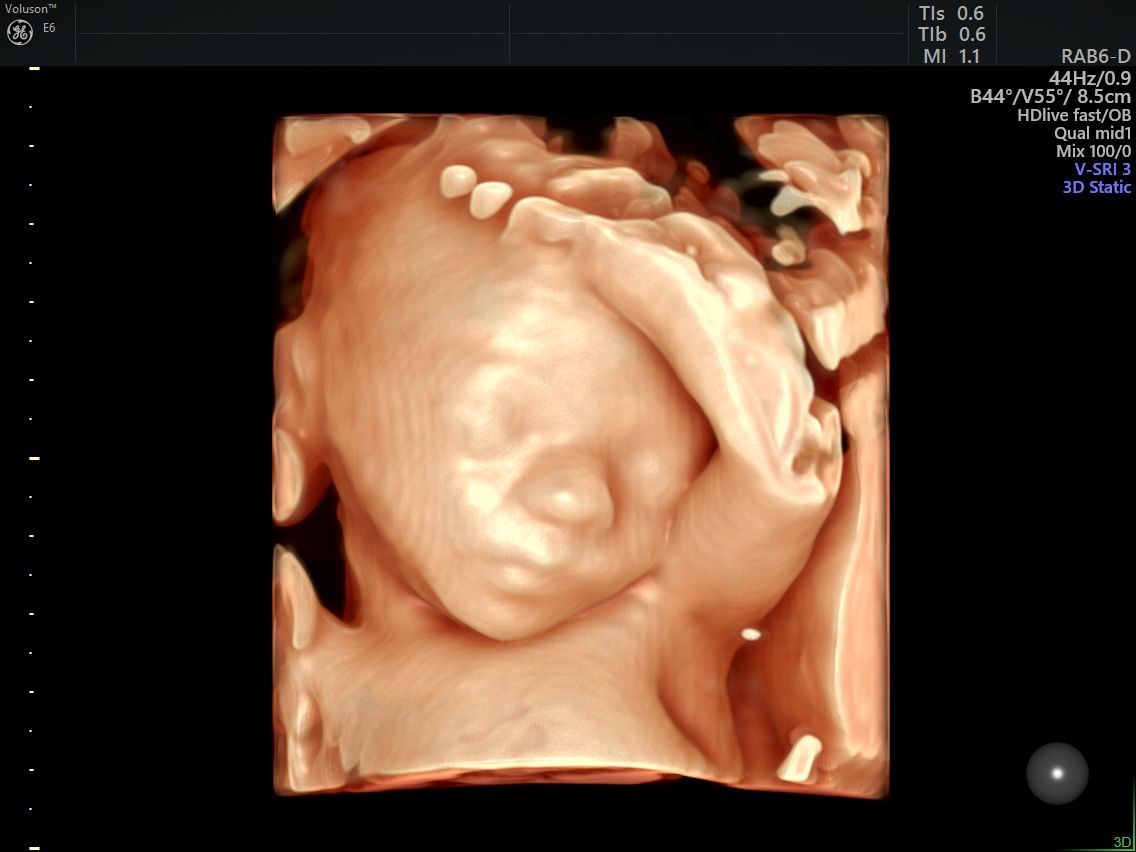

Realizo estudios con tecnología avanzada para detectar posibles complicaciones durante el embarazo. Entre ellos se incluyen ultrasonidos de tamizaje en el primer trimestre, ultrasonidos estructurales, seguimiento de embarazos gemelares y pruebas genéticas como ADN fetal, biopsia de vellosidades coriales y amniocentesis, que ayudan a evaluar la salud del bebé y del embarazo.

Fotos y videos